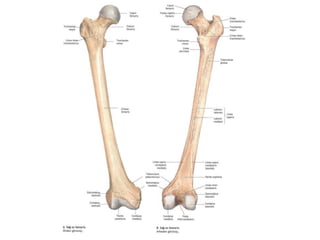

Humerus (kol kemiği)

Üst uç

• – Caput humeri

• – Tuberculum majus-minus

• – Collum anatomicum

• – Collum chirurgicum

Cisim

– Tuberositas deltoidea

– Sulcus nervi radialis

Alt uç

– Condylus humeri

• Trochlea humeri

• Capitulum humeri

– Fossa coronoidea

– Fossa radialis

– Fossa olecrani

– Epicondylus medialislateralis

• Sulcus nervi ulnaris

Humerus (kol kemiği) Üstuç • – Caput humeri • – Tuberculum majus-minus • – Collum anatomicum • – Collum chirurgicum Cisim – Tuberositas deltoidea – Sulcus nervi radialis Alt uç – Condylus humeri • Trochlea humeri • Capitulum humeri – Fossa coronoidea – Fossa radialis – Fossa olecrani – Epicondylus medialislateralis • Sulcus nervi ulnaris